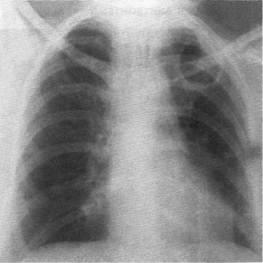

În multe cazuri, umbrele închise în formă de inel (iluminări închise limitate) sunt determinate în cazurile de infecție cu tuberculoză. La locul infiltrării țesutului pulmonar, se formează cel mai adesea cavități caracteristice ale cariilor de descompunere - caverne. Semnele radiografice ale tuberculozei pulmonare cavernoase sunt:

• prezența unei singure nuanțe circulare de formă rotundă sau ovală, cu contur exterior exterior clar și mai puțin distinct - o cavitate umplută cu aer (Figura 4);

• fluidul din cavitate, de regulă, nu este determinat. Grosimea peretelui cavității nu depășește de obicei 2-3 mm;

• în jurul cavernei pot fi mai multe puncte focale separate

ea, o ușoară etanșeitate fibroasă;

• Locația preferată a cavității este lobul superior al plămânilor și segmentul 6.

Fig. 4. X-ray a pacientului X. 46 de ani, într-o proiecție directă. În lobul superior al plămânului stâng, se definește o cavitate formată "uscată" cu un contur interior distinct interior și mai puțin distinct - o cavitate. Caucazul tuberculozei plămânilor